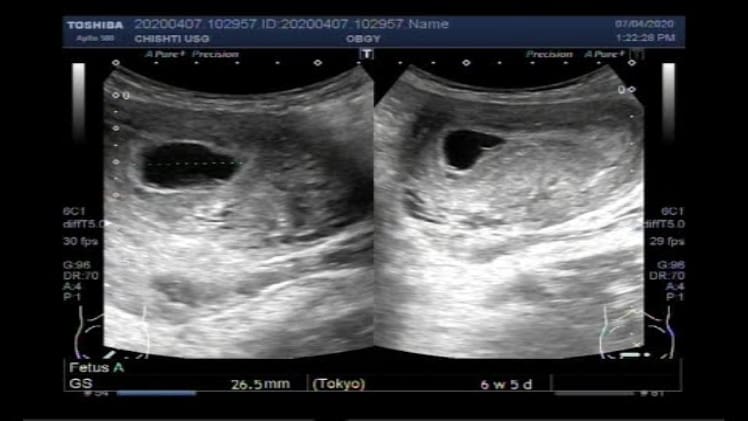

A blighted ovum, also known as an anembryonic pregnancy, is a type of miscarriage that occurs when a fertilized egg fails to develop into an embryo. The egg stops growing and the pregnancy typically ends in a miscarriage. This type of miscarriage typically occurs very early in the pregnancy, usually within the first few weeks.

A blighted ovum usually stops growing around the fifth week of pregnancy. It is important to note that this is an approximate timeline and can vary from woman to woman. In some cases, the egg may stop growing even earlier in the pregnancy.